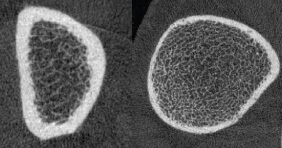

The Musculoskeletal Quantitative Imaging Research (MQIR) group consists of faculty members, postdoctoral fellows, research staff, and medical and graduate students who pursue their passion for teaching and research in quantitative tissue characterization focused on the musculoskeletal system.

Musculoskeletal Quantitative Imaging Research Directions